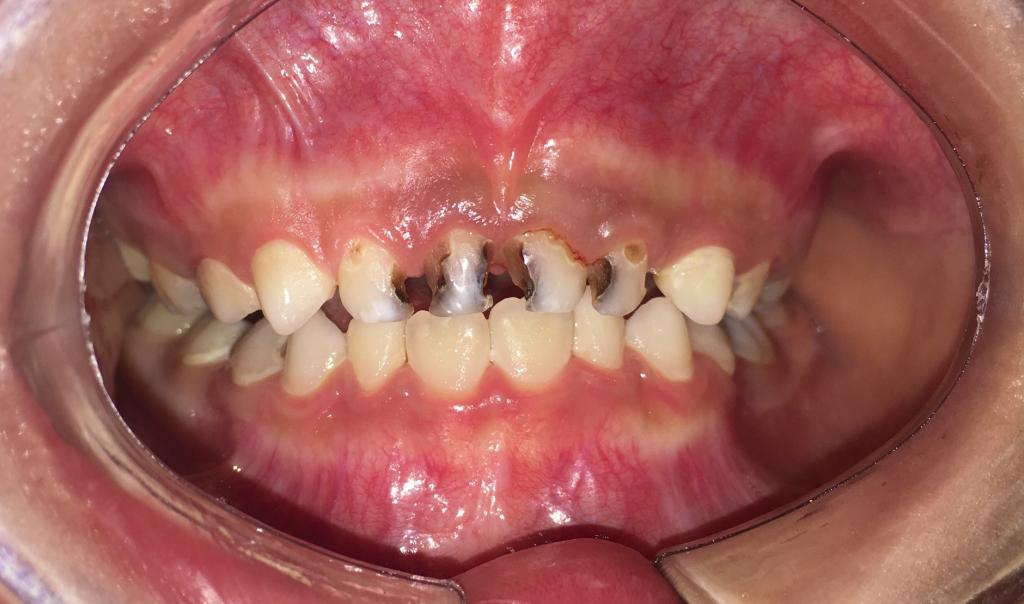

吃糖的最大坏处就是容易导致蛀牙,糖摄入过多,加上不注意口腔卫生致使食物残渣残留,糖会被细菌分解发酵,产生酸性物质,侵蚀牙齿,使牙齿遭到破坏。预防宝宝蛀牙,糖是头号大敌。

致病的糖,不止指名称上带“糖”字的食物,更多的是隐身于各种食物中,尤其是深受宝宝们喜爱的各种零食,如巧克力、冰淇淋、饼干、蛋糕等等。让宝宝少吃甜食和膨化食品,小心食物中的“隐形糖”,不能让孩子养成把饭含在口中、边吃饭边玩的习惯,因为米饭中同样含有糖分。